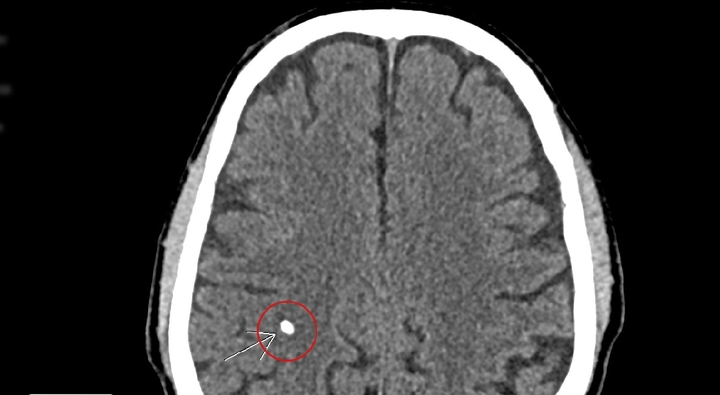

Chóng mặt, đau đầu, người đàn ông đi khám được bác sĩ kiểm tra phát hiện rải rác các di chứng ấu trùng sán não, kèm theo tổn thương viêm đa xoang.

Do có thói quen hay ăn tiết canh, thịt chua nên dù sán đã làm tổ trong não thành ổ, nhưng người này không biết cho đến khi đau đầu nhiều gây liệt nửa người.